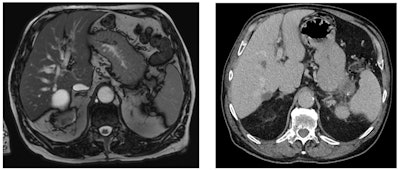

Abdominal and pelvic CT and MRI scans were independently reviewed by radiologists to develop an algorithm to categorize the missed cases and identify the most likely explanation for why they were missed.

The researchers found that in 10% of PIPC patients, imaging signs associated with pancreatic cancer, such as dilated bile or pancreatic ducts, were not recognized as such and not investigated further.

In the previous scans of 13 patients (26%), the signs of a mass lesion were not picked up by the radiologist, Umar added.

"The identification rate of pancreatic cancers are dictated by the size of the lesion and the amount of isoattenuating small tumors," explained Marti-Bonmati, who was made a gold medallist of the European Society of Gastrointestinal and Abdominal Radiology in 2018. "The imaging technique is critical to the success in identification of pancreatic cancers."

In CT, the dose concentration and rate of contrast administration are vitally important to identify pancreatic tumors, and the use of spectral CT or dual-energy CT scanners can help to pick up isoattenuating tumors at low or standard energy, he pointed out. For further reading in this area, Marti-Bonmati recommends the recent "Insights into Imaging" article by Dr. Hongwei Liang and colleagues.

There is always a certain rate of missed cancers, sometimes because of underlying confounding factors, such as chronic pancreatitis mimicking or masking a mass, noted Dr. Rossano Girometti, associate professor of radiology at Udine University Hospital in Italy. "It can be a difficult diagnosis, even for the pathologist," he said.

He added that a pancreatic lesion may be missed because the case is inherently difficult, such as isodense cancers or cancers arising in a chronic pancreatitis context, and this can happen because of the nature of the lesion or pancreatic background.